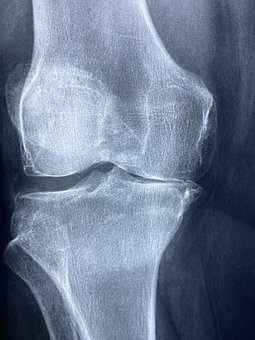

무릎 관절의 무릎 퇴행성 관절염의 진행 단계는 연골의 손상 정도에 따라 크게 4단계로 나눌 수 있습니다.

1 단계 증상이 시작돼 시큰한 통증이 생기지만 누워있거나 앉아서 쉬면 통증이 가라앉습니다.

2 단계 연골이 손상돼 무릎 관절 사이 간격이 좁아지면 염증이 생겨 무릎을 자유롭게 구부리고 펴기가 어렵습니다.

3 단계 증상은 뾰족한 뼈가 가시처럼 자라는 뼈가 있어어'골절'이 잇따라 발생해 통증이 자주 발생합니다.

4 단계말기 단계로 증상이 악화되면 연골 손상이 심하고 무릎 위아래 뼈가 거의 닿아 극심한 통증과 발열을 동반합니다. 한번 손상된 연골은 회복이 어려운 것이 사실입니다. 다만, 초,중반까지는 비수술적 치료를 통해 증상 개선을 기대할 수 있습니다. 따라서 의심 증상이 발생할 경우 조기에 전문의를 찾아 정확한 진단과 관리를 받는 것이 증상악화를 줄이는 무릎 퇴행성 관절염 치료의 핵심입니다.